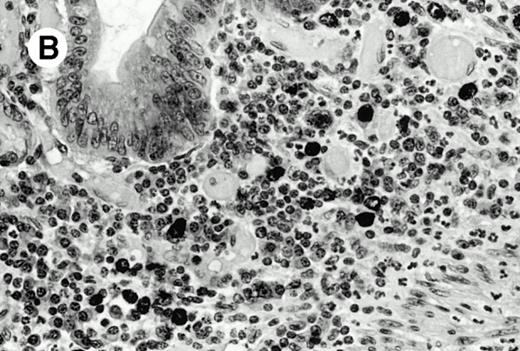

Subcutaneous γδ T-cell lymphoma (case no. 6). (A) Initial biopsy sample shows characteristic features of cytophagic histiocytic panniculitis without evidence of lymphoma cells; (B) second biopsy performed 7 months later demonstrates involvement of the subcutaneous tissue by a pleomorphic γδ T-cell lymphoma (hematoxylin-eosin stain).

Three cases (cases no. 1 to 3) were located in the nasal cavity. The neoplastic infiltrate consisted of medium and/or large pleomorphic lymphoid cells (Fig 1)intermingled with variable numbers of small lymphoid cells, plasma cells, eosinophils, and histiocytes. Features of angiocentrism and angioinvasion, epitheliotropism, and areas of necrosis were observed in all three cases. Patient no. 4 presented with disease restricted to the lung and an open-lung biopsy was available. The neoplastic infiltrate was composed of large atypical lymphoid cells and was predominantly interstitial without extensive destruction of the normal architecture. Features of angiocentrism, angioinvasion, and epitheliotropism were present (Fig 2A and B). Case no. 5 involved the larynx, extending to the piriform sinus, the ventricle, and the arytenoid. One month later, the lymphoma disseminated to the subcutaneous tissue in the spinal region and biopsy specimens from both sites were available. The neoplastic cells were medium and large, with abundant clear cytoplasm and slightly irregular nuclei with dense chromatin. Epitheliotropism was present in the larynx mucosa. Small foci of necrosis and angiocentrism were seen without angioinvasion. Three patients presented with cutaneous disease. Cases no. 6 and 7 were comparable, as both histories started with necrotic subcutaneous nodules of the thigh, which on histologic analysis were characteristic of cytophagic histiocytic panniculitis without evidence of lymphoma (Fig 3A). Second excisional biopsies of cutaneous nodules obtained 7 and 5 months later, respectively, showed characteristic features of lymphoma in both cases (Fig 3B). However, in case no. 6, skin biopsy specimens showed an epidermotropic PML lymphoma extending to the dermis and the subcutaneous tissue, whereas in case no. 7, the neoplastic infiltrate consisted of a PSC confined to the subcutaneous tissue, admixed with benign histiocytes that showed phagocytosis. Patient no. 8 presented with recurrent skin lesions with spontaneous remission over a period of 10 years. The initial skin biopsies demonstrated an intense epidermotropic neoplastic infiltrate that extended to the superficial and deep dermis composed of atypical PML cells. All cutaneous cases displayed features of angiocentrism, but angioinvasion was observed only in case no. 6 and foci of necrosis in cases no. 6 and 8.